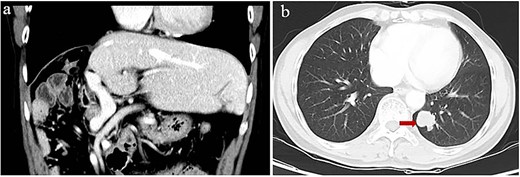

At 24 months after his admission with hepatic occupation, contrast-enhanced computed tomography detected intrahepatic recurrence, which was confirmed by magnetic resonance imaging. The patient was admitted again and given two cycles of transarterial chemoembolization (TACE), which achieved a partial response (PR) based on the Response Evaluation Criteria for Solid Tumors [18] (Fig. 2a and b). At 16 weeks after his second admission, the patient underwent right hemihepatectomy. Baseline variables before surgery are described in Supplementary Table 1. The surgery proceeded smoothly, and the patient recovered well. Postoperative histopathology revealed necrosis in more than 90% of the tumor, whereas no nodular cirrhosis, satellite nodules, or tumor emboli were observed. Instead, necrotic and proliferative fibrous tissue with multinucleated giant cells was observed, with abundant infiltration by lymphocytes and focal aggregation of neutrophils (Fig. 2c and d). Surrounding liver tissue showed chronic hepatitis changes (G2S2 on the inflammation and fibrosis scale) as well as hyperplasia of the small bile duct.

Intrahepatic recurrence and response to TACE. (a, b) Contrast-enhanced computed tomography in the (a) arterial phase or (b) venous phase after two cycles of TACE, showing PR of the recurrent tumor liver. (c, d) Histopathology of recurrent tumor after TACE at magnifications of (c) 40× or (d) 100×, showing necrosis of more than 90% of the tumor, proliferative fibrous tissue (leftward arrows), blue embolic agent in vasculature (rightward arrows), multinucleated giant cells, and abundant infiltration by lymphocytes (downward arrow).

Starting 1 month after repeat surgery, the patient received 200 mg of the ICI tislelizumab (BGB-A317; BeiGene, Beijing, China) once every 3 weeks via intravenous delivery lasting 60 min, in accordance with the manufacturer’s recommended dosing schedule. From 8 weeks on this therapy onwards, the level of alpha-fetoprotein in serum progressively increased. After 74 weeks on this therapy (21 treatments), the patient was diagnosed with Grade 2 hypothyroidism based on levels of thyroid hormone in serum and with Grade 2 pruritus based on signs and symptoms. Hypothyroidism was not treated because there were no obvious symptoms. However, he showed no signs of intra- or extrahepatic metastases in the entire body, abdomen, thoracic cavity, or brain based on magnetic resonance imaging or on contrast-enhanced, positron-emission, or bone-emission computed tomography. After 24 weeks on tislelizumab, a single metastasis was detected in the lung (Fig. 3). The patient was subjected to eight cycles of stereotactic body radiation therapy, and the level of alpha-fetoprotein in serum 3 weeks later was 275 ng/ml. Intensive follow-up continues.

Computed tomography of lung metastasis after 2 years of adjuvant ICI. (a) Imaging at the venous stage did not reveal obvious lesions in the residual liver. (b) Imaging of the left lower lung revealed a single tumor (arrow).